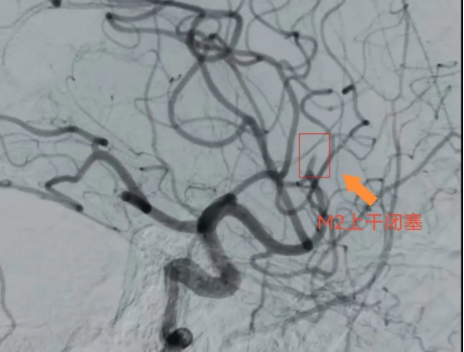

通过急诊MR及患者临床表现,初步判断责任血管在左侧大脑中M2段,如不及时处理,肢体偏瘫症状将持续加重,最终可能导致完全瘫痪并失语。

术中脑血管造影证实责任血管为左侧大脑中动脉M2上干闭塞。M2段血管取栓治疗属于MeVO取栓。

这类手术被称为“刀尖上的舞蹈”:一是M2上干管腔细小、路径迂曲,操作空间极小;二是血管壁脆弱,易破裂出血;三是若血管未及时开通,患者可能终身遗留神经功能缺损。